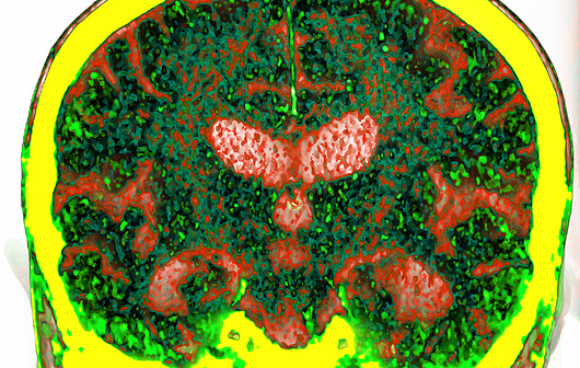

חתך של כלי דם במוח (שחור), דופנותיו מכילות תאי אנדותל צפופים. מסביבו תאי גלייה (ירוק) ותאי עצב (אדום). מחסום הדם-מוח | מקור: C.j.guerin, Phd, Mrc Toxicology Unit, Science photo Library